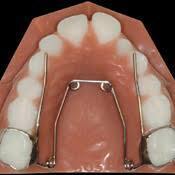

윗턱을 좌우로 벌리는 데 약한 손잡이인 어금니에 약한 힘(quad helix)만 가해도 윗턱은 좌우로 분리된답니다.

quad-helix같이 상악치아에 약한 힘을 가하는 확장장치만으로도 윗턱뼈는 좌우로 분리됩니다.

너무 어린 나이에 RPE같이 치아에 강한 힘을 가하는 확장장치를 사용하면 코의 변형이나 코아래조직의 울혈(출혈이 생겨 피부아래에 비춰보이는 현상)이 생길 수도 있으므로 유년기의 상악확장은 치아에 약한 힘을 가하는 quad-helix같은 가벼운 확장장치의 사용이 추천됩니다.